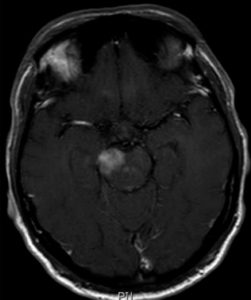

Doença de Neuro-Behçet mimetizando um tumor cerebral

Doença de Behçet é uma síndrome multissistêmica inflamatória de etiologia desconhecida com períodos de relapso e remissões. A condição foi nomeada em memória de Hulusi Behçet, um dermatologista turco o qual descreveu uma tríade de sintomas, caracterizada por úlceras orais recorrentes, úlceras genitais e uveíte. Posteriormente, estudos demonstraram o padrão multissistêmico dessa condição, a qual pode comprometer vasos, articulações, o trato gastrointestinal, o coração, pulmões e o sistema nervoso central (SNC). A doença pode afetar todos os tipos de vasos sanguíneos, tanto a parte arterial quanto a venosa. Poucos casos de DNB mimetizando um tumor cerebral foram reportados. Nós ilustramos um caso de um paciente com um diagnóstico prévio de tumor cerebral- o qual foi diagnosticado como DB. Nós discutimos o caso e revisamos a literatura considerando essa apresentação rara de DB.

Doenca de neuro behcet mimetizando um tumor cerebral